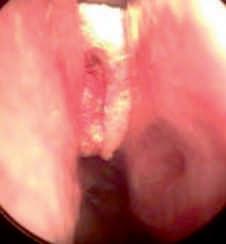

• SURGISPON" is effective in supporting the new graft in the outer ear canal after tympanoplasty and buttressing middle ear implants